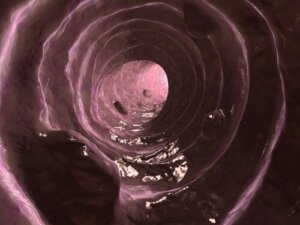

Slijm is een stof die door het darmslijmvlies wordt afgescheiden – vergelijkbaar met de stof die door het epitheel van de luchtwegen wordt geproduceerd – en die als functie heeft de bekleding van de dikke darm gesmeerd en vochtig te houden.